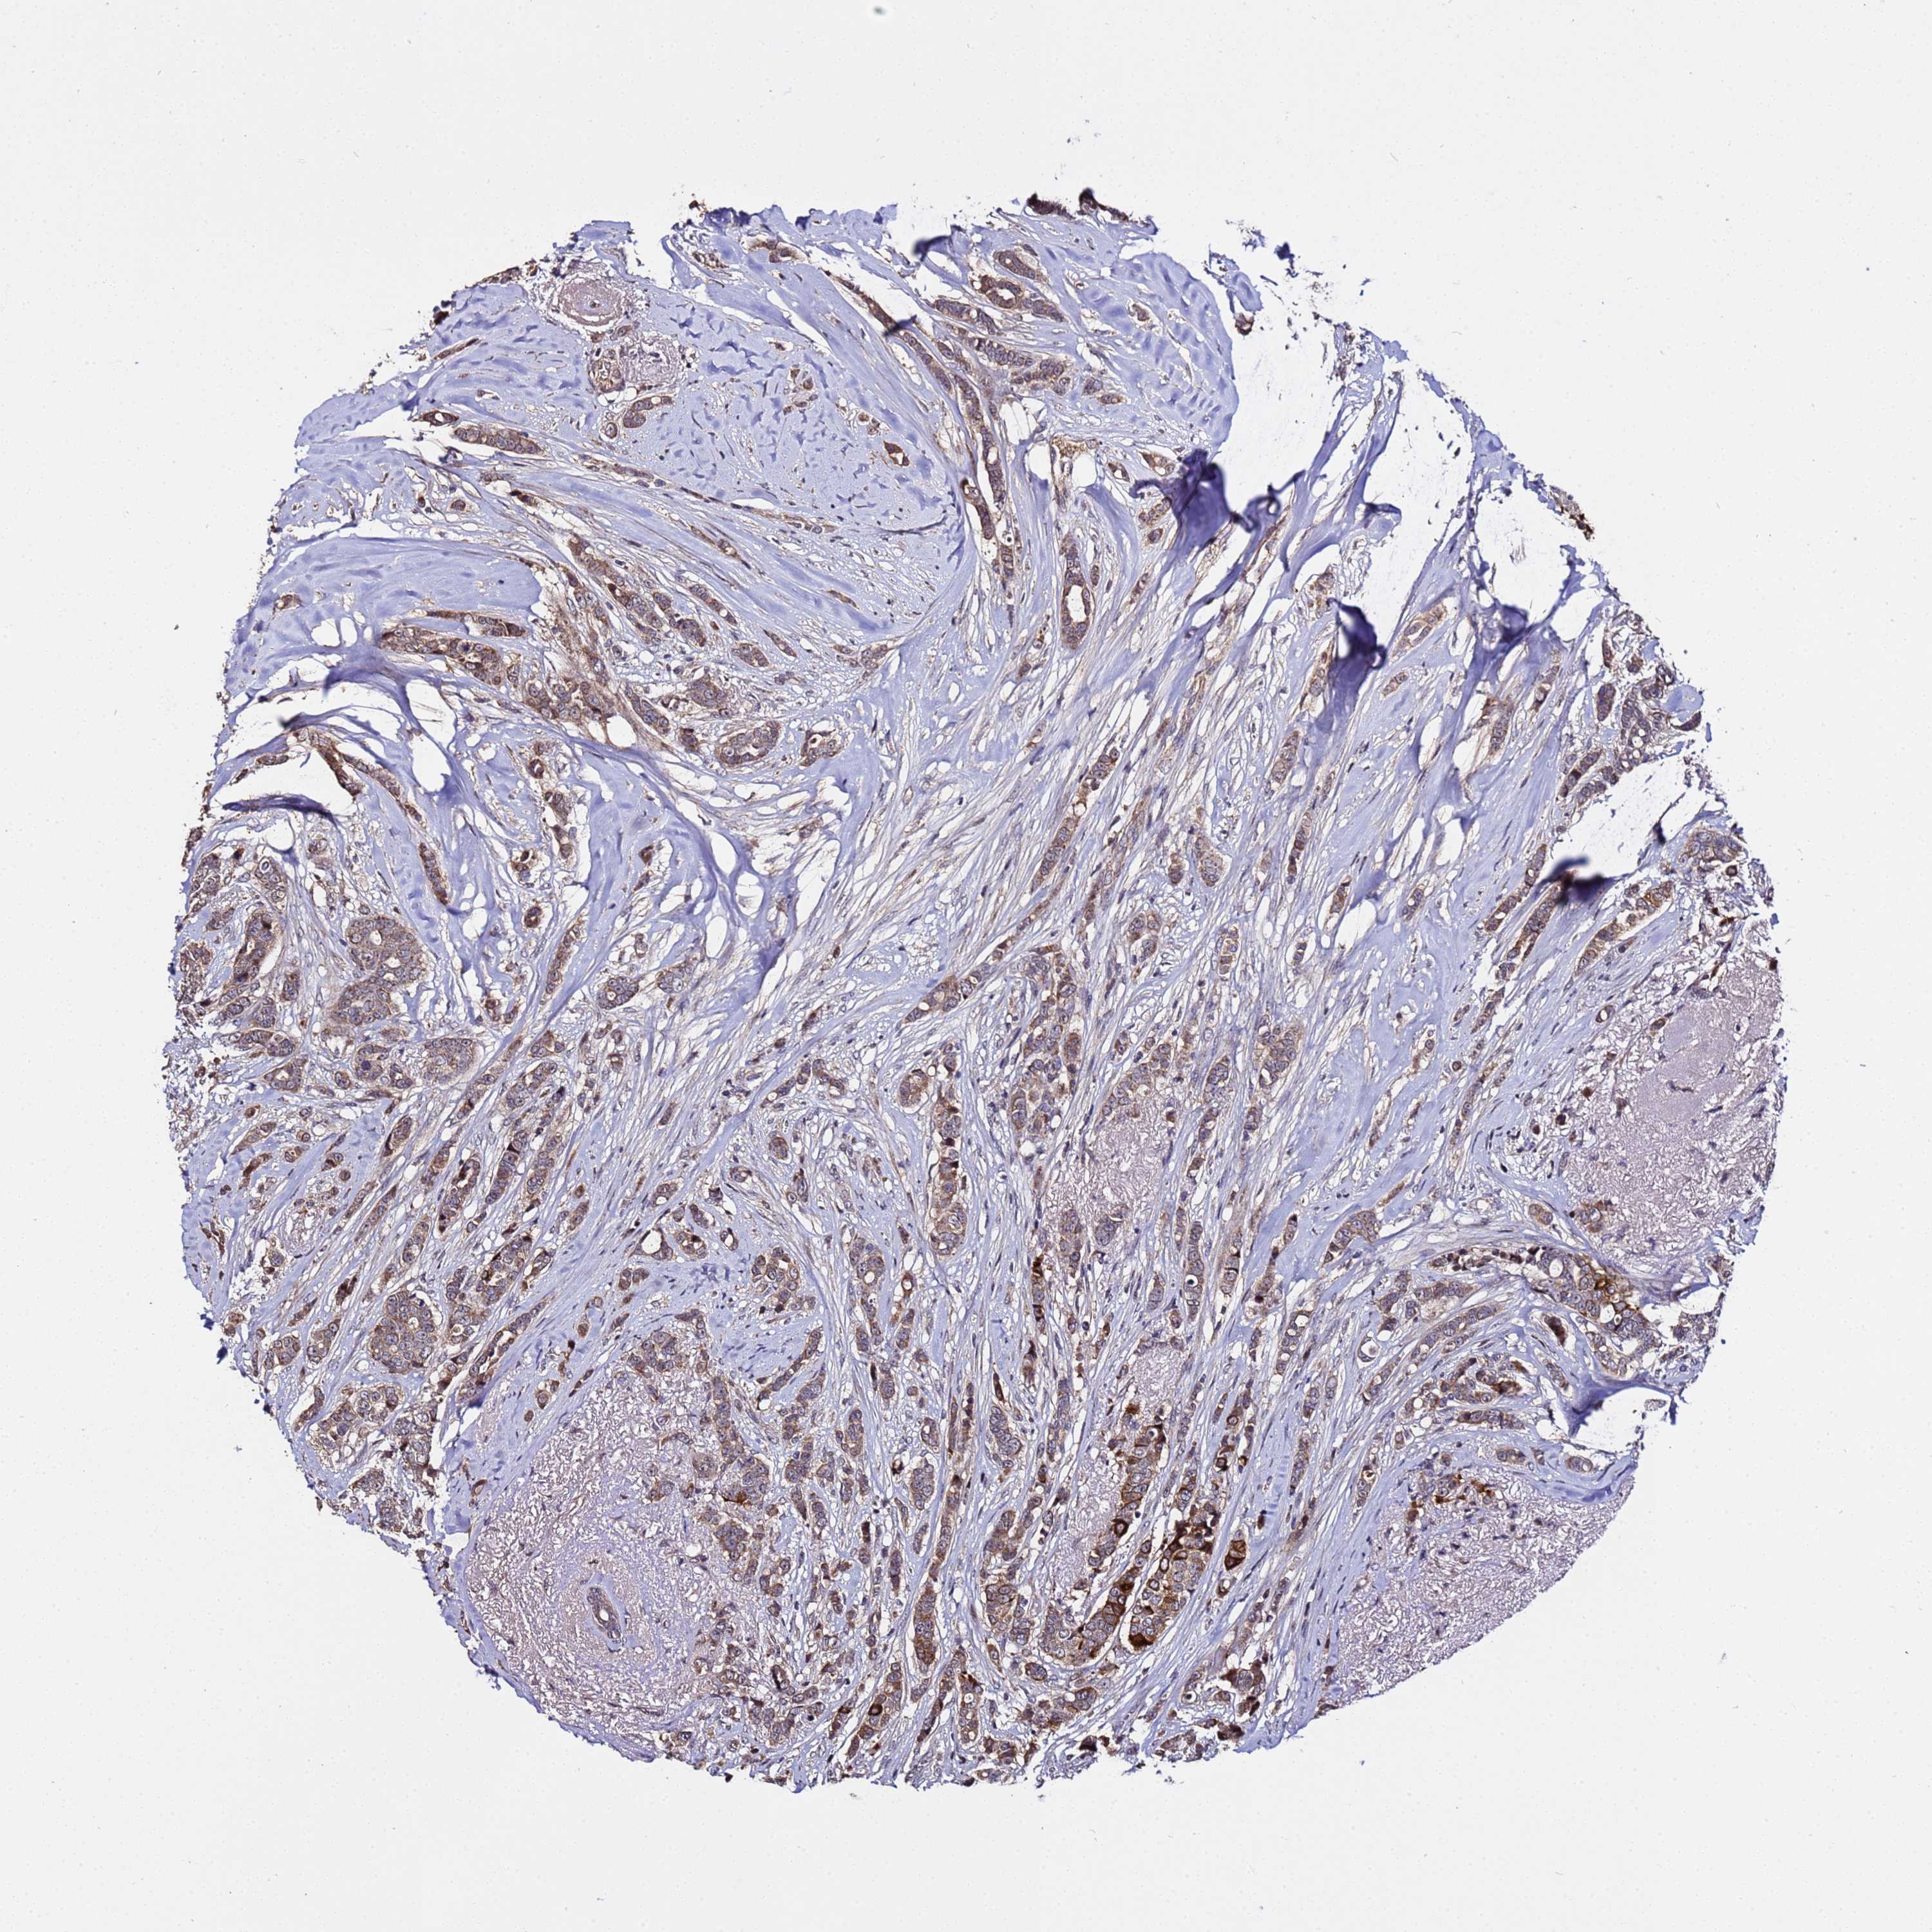

CANCER BREAST CANCER Show tissue menu

Breast cancer

Human cancer